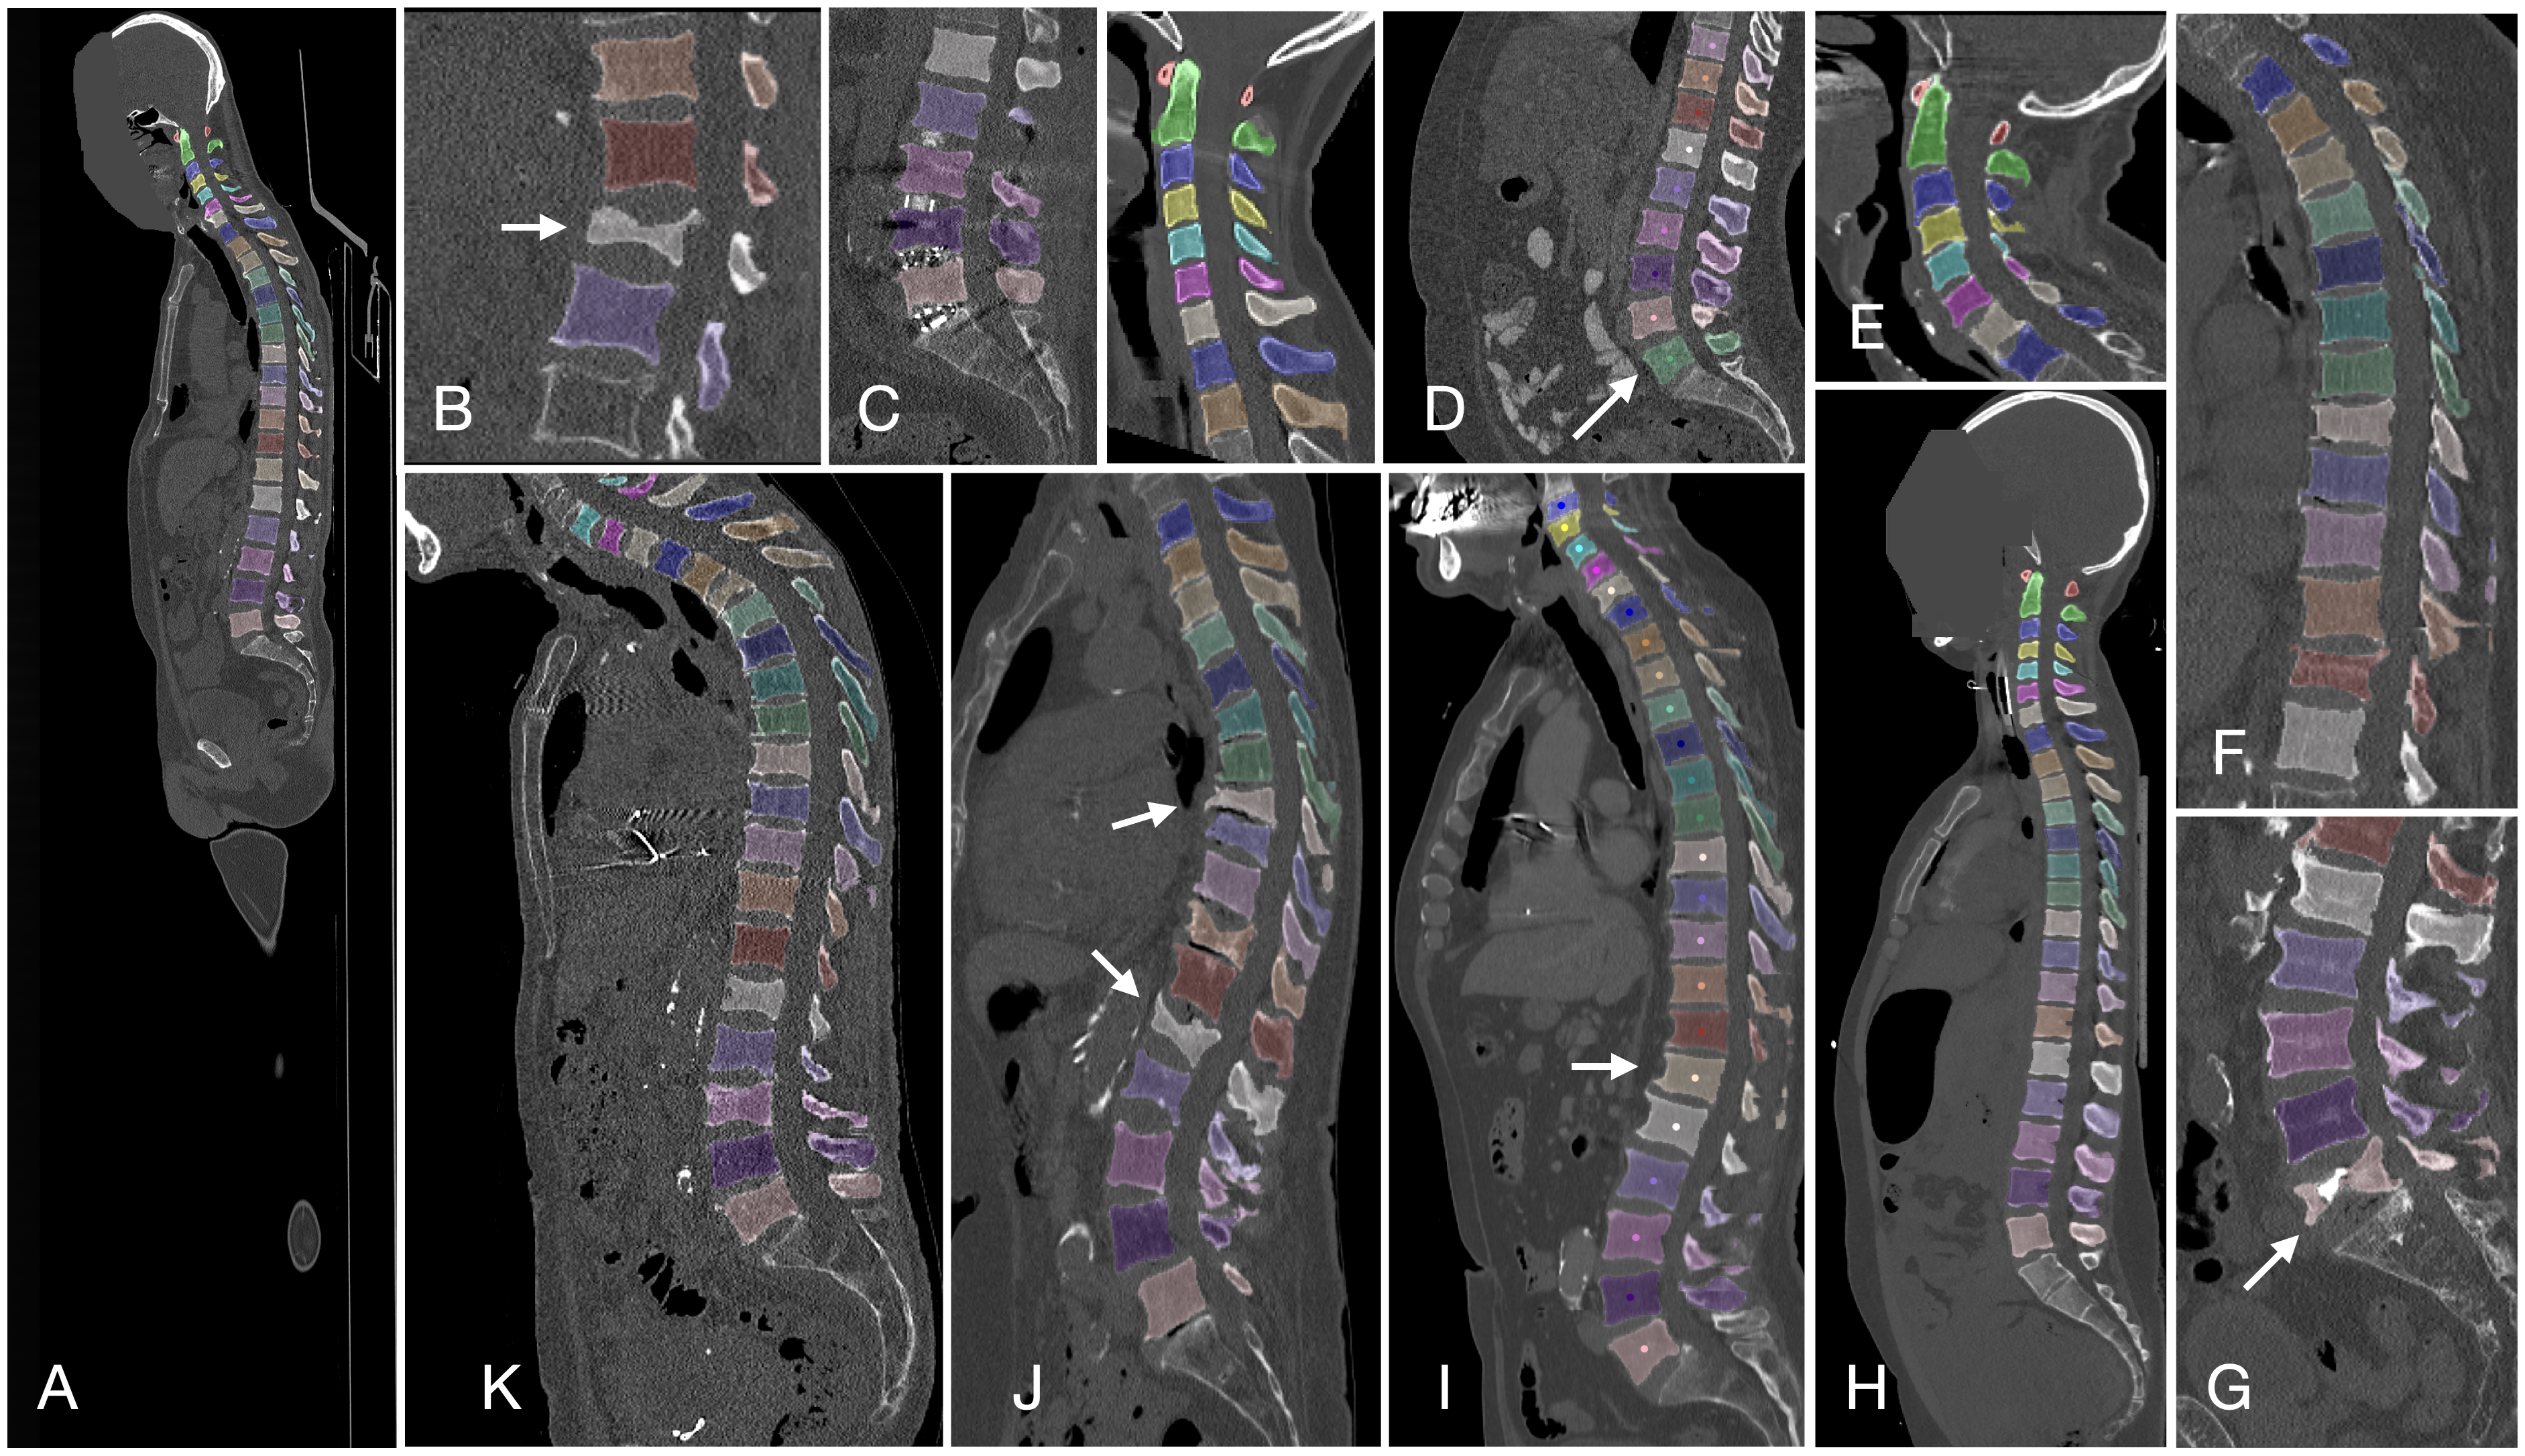

Verse大规模脊椎分割数据集

| 名称 | 标注内容 | 类型 | 模态 | 数量 | 标签格式 | 文件格式 | License |

|---|---|---|---|---|---|---|---|

| VerSe | 脊椎 | 分割 | CC BY-SA 4.0 |